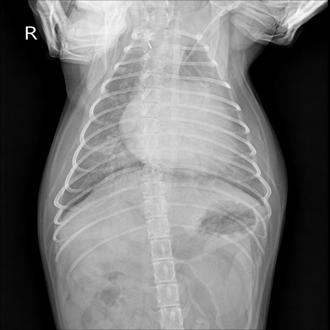

심부전

심부전은 초기에는 기침이나 숨이 차 보이는 증상처럼 일상적인 변화로 시작되는 경우가 많습니다. 하지만 진행될 경우 호흡 곤란과 활동성 저하로 생활의 질에 큰 영향을 미칠 수 있습니다.

심장 기능과 폐 상태를 종합적으로 평가한 뒤 약물 조절과 생활 관리, 보호자가 주의해야 할 신호까지 함께 안내해 아이의 일상이 무너지지 않도록 관리합니다.